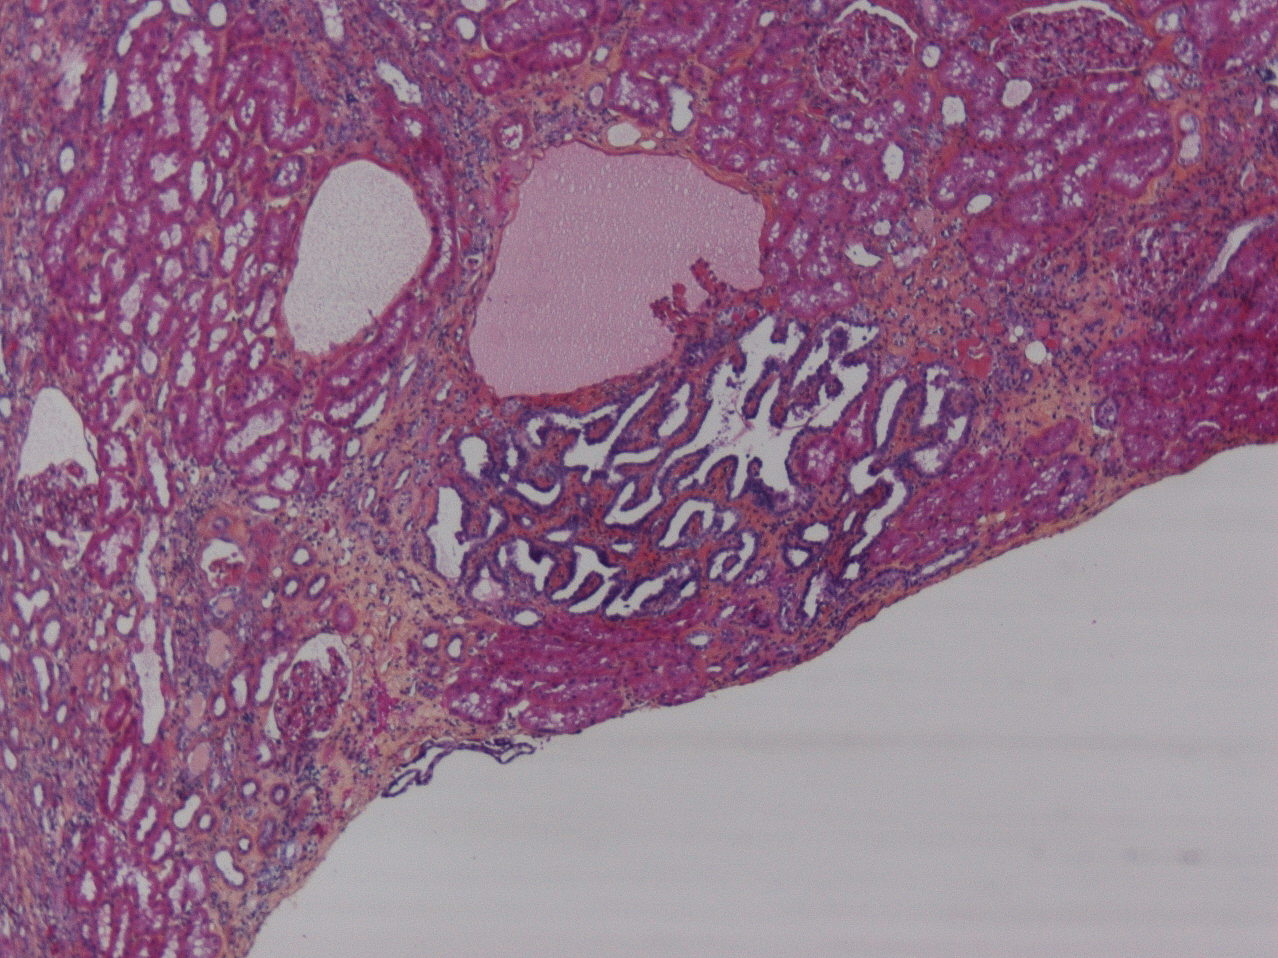

Consensus grade: Renal adenoma

Case description (by case creator):

adenoma